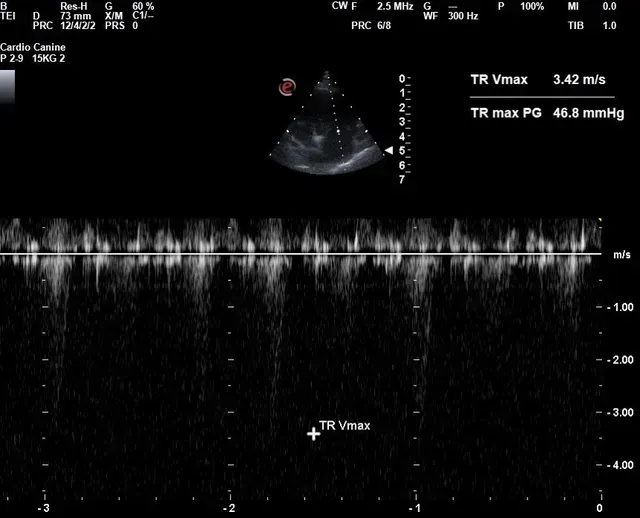

Echocardiogram (Cardiac Ultrasound)

- Used to evaluate heart size and functionality, including:

- Valve appearance

- Contraction strength

- Identification of congenital defects